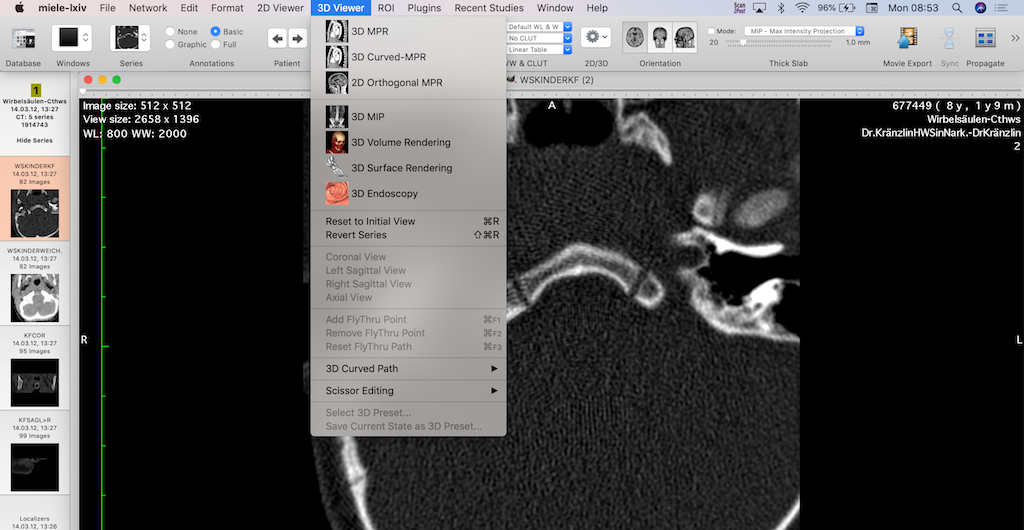

Open-source alternatives, such as Orthanc, Horos, OsiriX, 3D Slicer, and Miele-LXIV, were born out of a need to overcome these barriers. These tools have grown thanks to their active communities and the involvement of healthcare professionals who understand the field’s unique challenges.

Take Horos and Miele-LXIV for instance. Both are robust DICOM viewers tailored for macOS users. Horos, in particular, has gained significant traction among radiologists, researchers, and educators for its user-friendly interface and customization options.

- Start Small: Begin with a specific use case, such as a DICOM viewer like Horos or Miele-LXIV, to assess compatibility and usability.